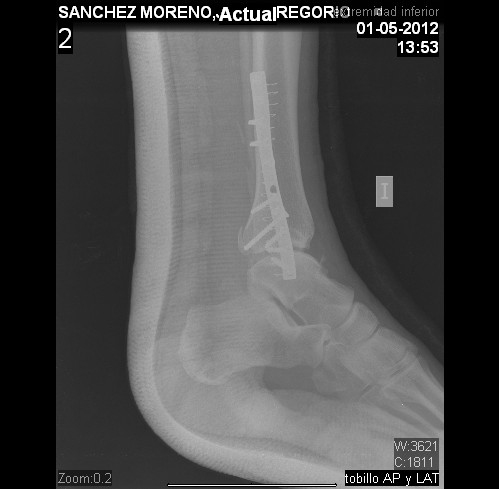

Os enseño las Radiografías de Robocot. En dos o tres meses me quitan el tornillo largo transversal, pero me digo el Trauma que no hace falta ingreso,y menos mal porque soy malísimo enfermo en los Hospitales.

En resumen operación con luxación-fractura de peroné, ligamentos rotos, placa con 10 tornillos, 4 de ellos corticales me lo tienen que volver a sacar pronto. Os pongo alguna foto donde se aprecia los 6 tornillos que van al peroné, los otros 4 son para ligamentos. O sea que este año seré IRONMAN, por los tornillos que llevo, y no por hacer la prueba en sí, Adios Medio Ironman Valencia, Elche y Ironman Frankfurt. Pero espero volver.